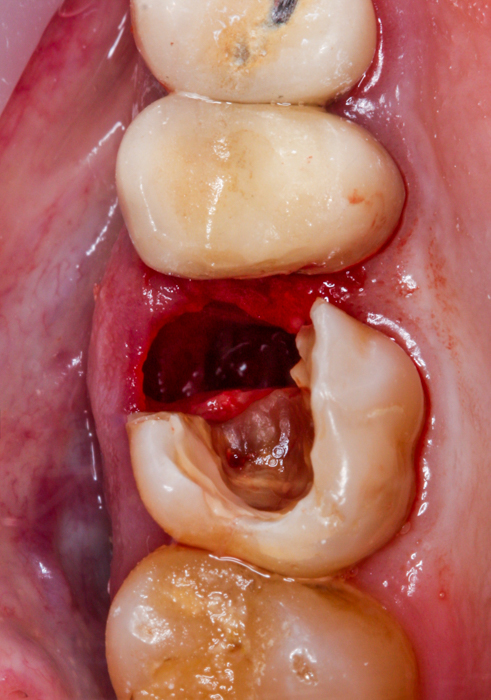

Tak właśnie było w przedstawionym poniżej przypadku – w korzeniu policzkowym bliższym zęba uprzednio leczonego kanałowo znajdował się bardzo głęboko schodzący poddziąsłowo ubytek próchnicowy, sięgający niemal brzegu kości, ponadto torbiel okołowierzchołkowa i widoczny, spowodowany być może stanem zapalnym wokół zęba, odczyn w zatoce szczękowej, manifestujący się pogrubioną błoną śluzową. Po dokładnej diagnostyce radiologicznej wspartej badaniem tomograficznym CBCT i omówieniu z pacjentem wszystkich możliwych wariantów wraz z wynikającymi z nich korzyściami i ryzykiem, wybór padł na radektomię.

W znieczuleniu miejscowym, z użyciem mikroskopu, maleńkim wiertłem odcięty został uszkodzony korzeń tak, aby w możliwie najmniejszym stopniu uszkodzić fragmenty zęba, które mają pozostać w jamie ustnej pacjenta oraz otaczającą je kość. Następnie, niezwykle ostrożnie, usunięto odpreparowany korzeń, wyłuszczono w całości torbiel i założono szew stabilizujący powstający w zębodole skrzep. Pozostałą część zęba zabezpieczono materiałem kompozytowym do czasu, gdy będzie możliwe wykonanie powtórnego leczenia kanałowego i ostateczna odbudowa części koronowej.